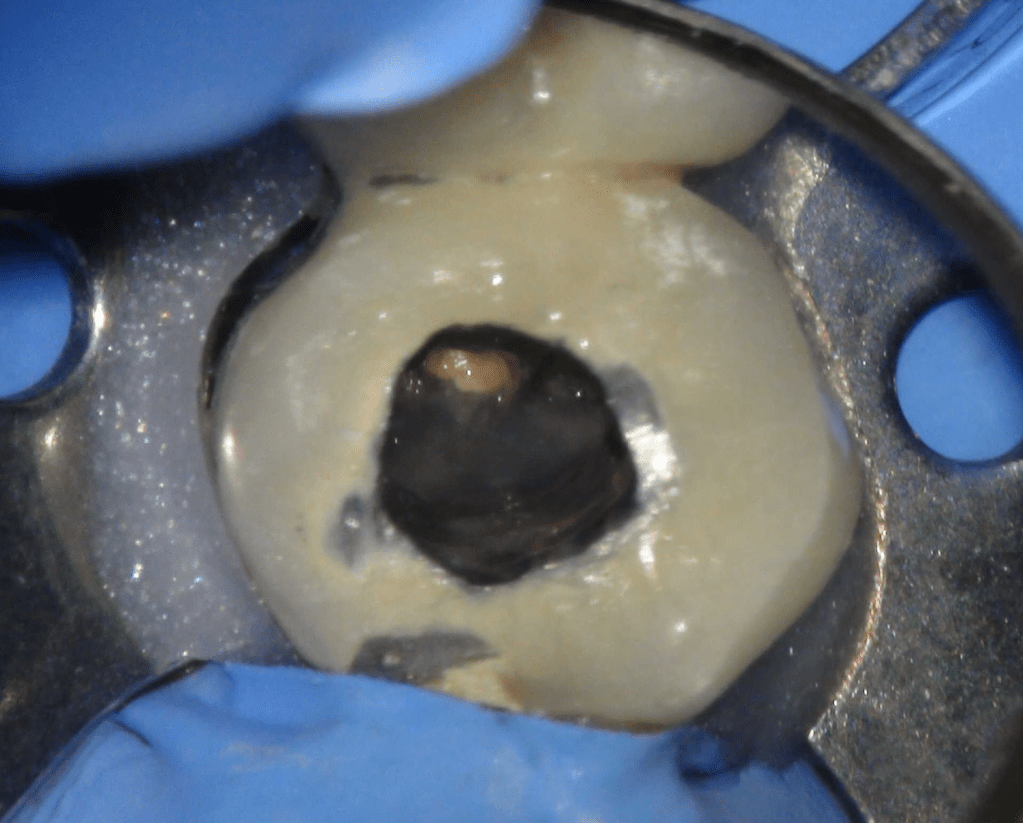

CALCIFICADOS

Premolar calcificado lesion